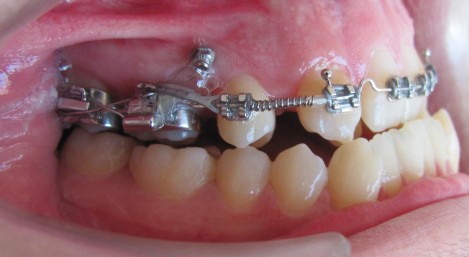

Ролята на мини имплантите при усложнени ортодонтски лечения

С навлизане на микроимплантите в ортодонтията, клиниката се разви в насока ползване резистентноста на костта спрямо по-големи сили прилагани при тежки случаи. Получените големи сили се ползват на къси разстояния, което дава възможност за контрол на посоката и големината й. Различната форма на главичката на винта позволява към него да се включват различни допълнителни приспособления, които улесняват клиничната работа и дават възможност за сегментни лечения.

Приложение на микро импланти в ортодонтията при ортодонтски млади и възрастни пациенти – сегментни решения

През последните няколко години в световен мащаб се разви ново направление за ползването на коста като опора при ортодонтски движения на зъби, чрез включването й посредством микроимпланти.